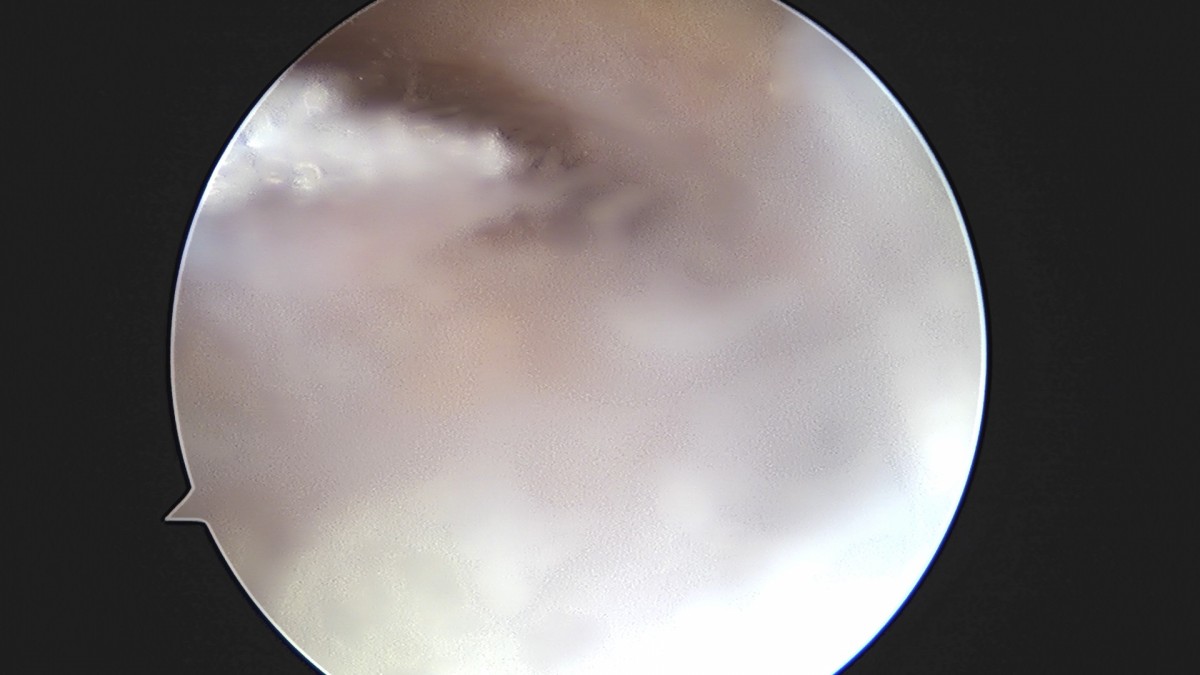

이재상원장님 무릎 반월상 연골판 절제술 장영O 환자

작성자 최고관리자 댓글 0건 조회 369회 작성일 25-09-16 16:02